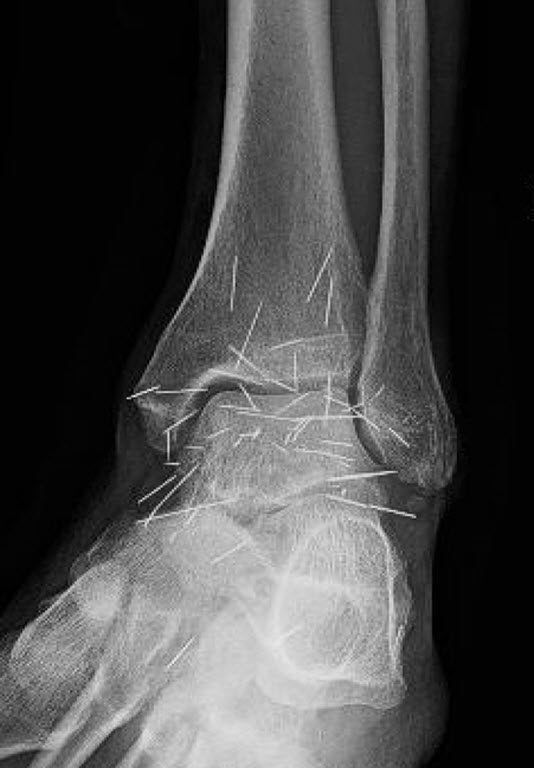

A 65-year-old woman from South Korea went to doctors for severe joint pain, and her X-ray ended up showing something very strange. The scan revealed hundreds of small gold needles left inside her knee tissue, and it stunned the medical team who looked at it.

Acupuncture uses thin needles placed in certain points on the body to ease pain. In her case the doctors said the gold needles were left inside on purpose, the idea being to give constant stimulation to the painful area.

There are more dangers too. If needles stay in the tissue they can block medical scans. The doctor also said: “They can obscure parts of the anatomy on an X ray.” He added that if a patient with metal fragments ever has an MRI, the magnets could make the pieces move and maybe even cut blood vessels.